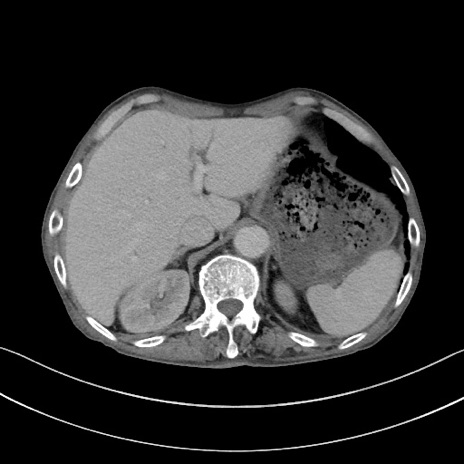

症例3(横断像)

症例

【症例】 70歳代男性

【主訴】右鼠径部腫瘤、疼痛

【現病歴】本日朝より上記主訴あり、受診。

【既往歴】膀胱癌にて膀胱全摘、両側尿管皮膚瘻

【データ】WBC 5600、CRP 0.56